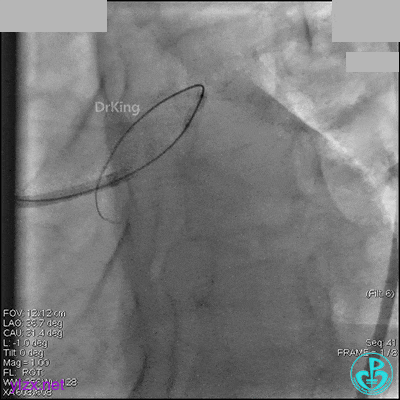

右冠脉中段充分扩张后欲植入3.5×38mm支架时,支架难以通过中远段扭曲处,且指引导管、导丝弹出飞扬。反复尝试导丝重新到达右冠脉远端时通过不顺利,局部造影剂滞留,远端血流接近3级。